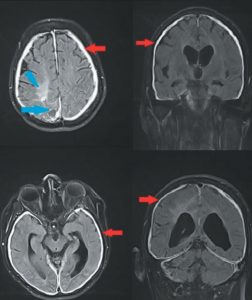

Une histoire de méninges

Nous rapportons le cas de madame G, 82 ans, hospitalisée dans notre service pour des troubles de la vigilance. Le principal antécédent est un cancer du sein droit diagnostiqué en…